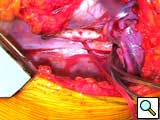

- The cardiac apex is positioned for placement of the inflow sewing ring. Even in the sickest patients, a small laparotomy pad can be placed infero-posteriorly to elevate the heart. The left anterior descending artery and apical insertion site are identified (Figure 4). In general, the sewing ring is positioned much like other LVADs. We opt for a slightly anterior apical position and attempt to have the device lay 1-2 cm away from and parallel to the ventricular septum. Teflon felt pledgets are cut to size and 2-0 braided polyester sutures are placed circumferentially. Depth of suture penetration is dependent in part on the thickness and sturdiness of the myocardium. In general, deep but not full thickness bites should be taken. These sutures are typically placed in quadrants with the sewing ring, aimed towards the aortic valve, being tied down after the first 2-3 sutures are placed. Great care should be used when tying these sutures, especially in patients with a recent myocardial infarction or dilated myopathies where tissue integrity could be quite weak. Typically, 12 sutures are required (with an occasional buttress suture as needed (Figure 5).